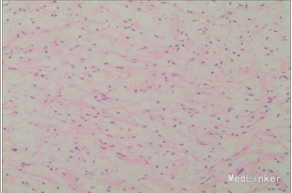

诊断 处理

完善相关检查,在气管插管麻下行“左额眶部占位病变切除术”。术后病理诊断为“(左眼眶)丛状神经纤维瘤”。术后给予患儿脱水、营养脑神经、抗感染等对症治疗。复查CT未见明显异常。

患儿术后2周左眼睑下垂较术前好转。双侧瞳孔反射、眼球活动均无异常。 丛状神经纤维瘤主要发生于眼睑,在出生后或幼年时期即出现症状和体征。侵袭范围广泛,包括眼睑、眶内软组织、眶骨和邻近的脑、颞部等。眼部最早和最多见为上、下睑软性肥厚,皮下瘤组织增生,使上、下睑隆起。眼睑皮肤常有淡棕色色素斑,眼球向前突出和向下移位。眼球突出虽然很显著,但向眶内纳入并不困难。肿瘤组织可直接侵袭眶内各种结构,上睑提肌首先被波及,引起上睑下垂,上举不足或不能。MRI可准确显示病变的范围尤其显示病变与邻近结构的关系,也可清楚显示其他部位伴发的肿瘤,但难以清晰显示眶壁骨质改变。手术治疗是必要的,手术切除应注意以下问题:1.眼睑病变的切除;2.眶内病变的处理;3.提上睑肌的处理;4.眶骨缺失的处理。丛状型术前诊断容易,但治疗较为棘手,易复发。